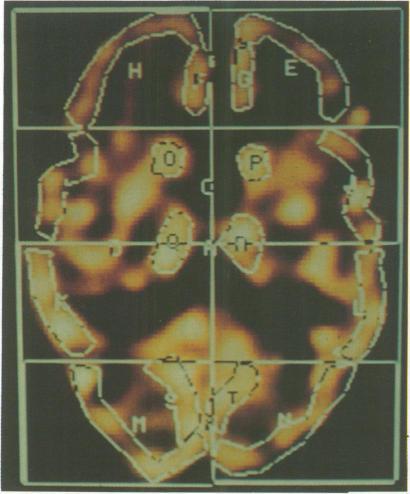

Thirty five patients with dementia of the Alzheimer type (DAT) and 35 controls matched for age, sex and handedness were investigated using single photon emission computer tomography (SPECT) with 99m technetium HMPAO. Regional cerebral blood flow (rCBF) was assessed semi-quantitatively in 18 cortical and 4 subcortical areas by normalising mean information density in each region to cerebellar mean information density. Analysis revealed significantly reduced rCBF to temporal, parietal, frontal and left occipital cortex in the patients whilst blood flow to subcortical areas showed no differences between the 2 groups. In addition, significant left-sided cortical hypoperfusion was seen in the DAT group but not in controls. When patients were sub-divided on the basis of disease severity, those with mild disease showed temporal, parietal and left frontal changes with more severely affected patients also showing right frontal and left occipital involvement. rCBF patterns did not distinguish between presenile and senile onset cases once duration and severity of illness were controlled. Eight cortical areas were also rated visually for perfusion deficits on a simple 4 point scale. Perfusion deficits were detected in 34 of 35 patients but in only 4 of 35 controls. In the DAT group significant correlations were found between many of the neuropsychological tests used and rCBF. Memory correlated with left temporal activity, praxis, perception, object assembly and block design with right parietal activity and language with activity throughout the left hemisphere. Significant correlations were also seen between subcortical and cortical blood flow, possibly explaining the correlations observed between many of the neuropsychological tests and thalamic blood flow.

对35例阿尔茨海默型痴呆(DAT)患者以及35例在年龄、性别和利手方面与之匹配的对照者,使用锝-99m六甲基丙烯胺肟(99mTc-HMPAO)单光子发射计算机断层扫描(SPECT)进行研究。通过将每个区域的平均信息密度与小脑平均信息密度进行归一化,对18个皮质区域和4个皮质下区域的局部脑血流量(rCBF)进行半定量评估。分析显示,患者颞叶、顶叶、额叶和左侧枕叶皮质的rCBF显著降低,而两组皮质下区域的血流量无差异。此外,DAT组出现显著的左侧皮质灌注不足,而对照组未出现。当根据疾病严重程度对患者进行细分时,轻度疾病患者表现出颞叶、顶叶和左侧额叶的变化,病情更严重的患者还表现出右侧额叶和左侧枕叶受累。一旦控制了病程和疾病严重程度,rCBF模式无法区分早老性和老年性发病病例。还使用简单的4分制对8个皮质区域的灌注缺损进行视觉评分。35例患者中有34例检测到灌注缺损,而35例对照者中只有4例检测到。在DAT组中,发现所使用的许多神经心理学测试与rCBF之间存在显著相关性。记忆力与左侧颞叶活动相关,运用、感知、物体组装和积木设计与右侧顶叶活动相关,语言与整个左侧半球的活动相关。皮质下和皮质血流量之间也存在显著相关性,这可能解释了许多神经心理学测试与丘脑血流量之间观察到的相关性。